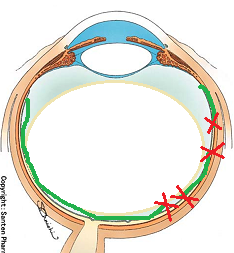

黒目(角膜)から入ってきた光は、目の奥の方のフィルム(網膜)に当たります。網膜は一つの束(視神経)になって、最終的には脳ミソにつながり、「物が見える」という事になります。

図の赤矢印の部分は視神経乳頭と言って、網膜が集まって束になる部分なのですが、実はこの部位のみ光を感じ取ることはできないのです。

自覚的には、マリオット盲点(視野が欠けて見えない部分)は、視界の中央から少し外側に存在します。(正確には、中心部から外側に15度位の部位)